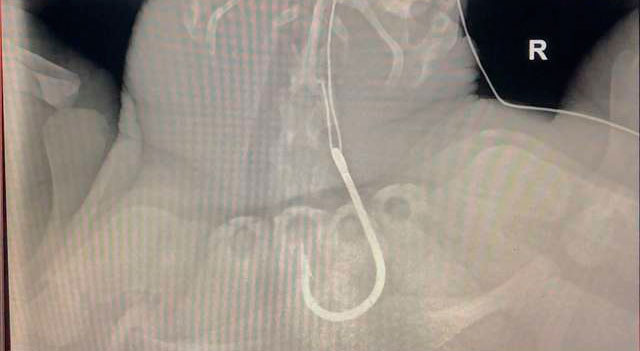

Спасатели, приехавшие на место, смогли погрузить черепаху в машину и отвезти в клинику. Черепахе сделали несколько рентгеновских снимков, которые показали, что внутренние органы не пострадали.

«Ей невероятно повело. Крючок не задел важные органы и артерии и попал в кишечник» Врачи решили провести операцию, чтобы извлечь крючок. К счастью она прошла гладко.